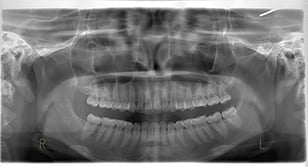

今まで歯科のレントゲン診断は全て平面で情報が得られないため、本来ある病変がレントゲン像では重なって覆い隠されてしまったり、立体的な位置関係がわからないため、限られた情報しか得られませんでした。

歯科用CTの導入により高解像度で立体像が得られるため、今までにない診断が得られるだけでなく、インプラント・矯正治療・精密根管治療・口腔外科手術なども今まで以上に安全に行えるようになりました。

CCDならびにCMOSセンサーによる完全デジタルレントゲンです。

フィルムシステムと比較して圧倒的に少ない被ばく線量で安心です。

ひずみの少ない像で顎全体が写るパノラマレントゲンのみならず、顎関節撮影、矯正治療で必要なセファロレントゲンも撮影できます。

フィルムを使わないレントゲンシステムを採用しています。

従来のフィルムと比較して少ない被ばく線量です。

また従来のフィルムレントゲンは徐々に黒くなっていき、長期保存性に難がありましたが、デジタルシステムによって、劣化の無い画像を永久に保存することが可能となりままた現像液などの廃液が発生せず、環境にもやさしいシステムです。